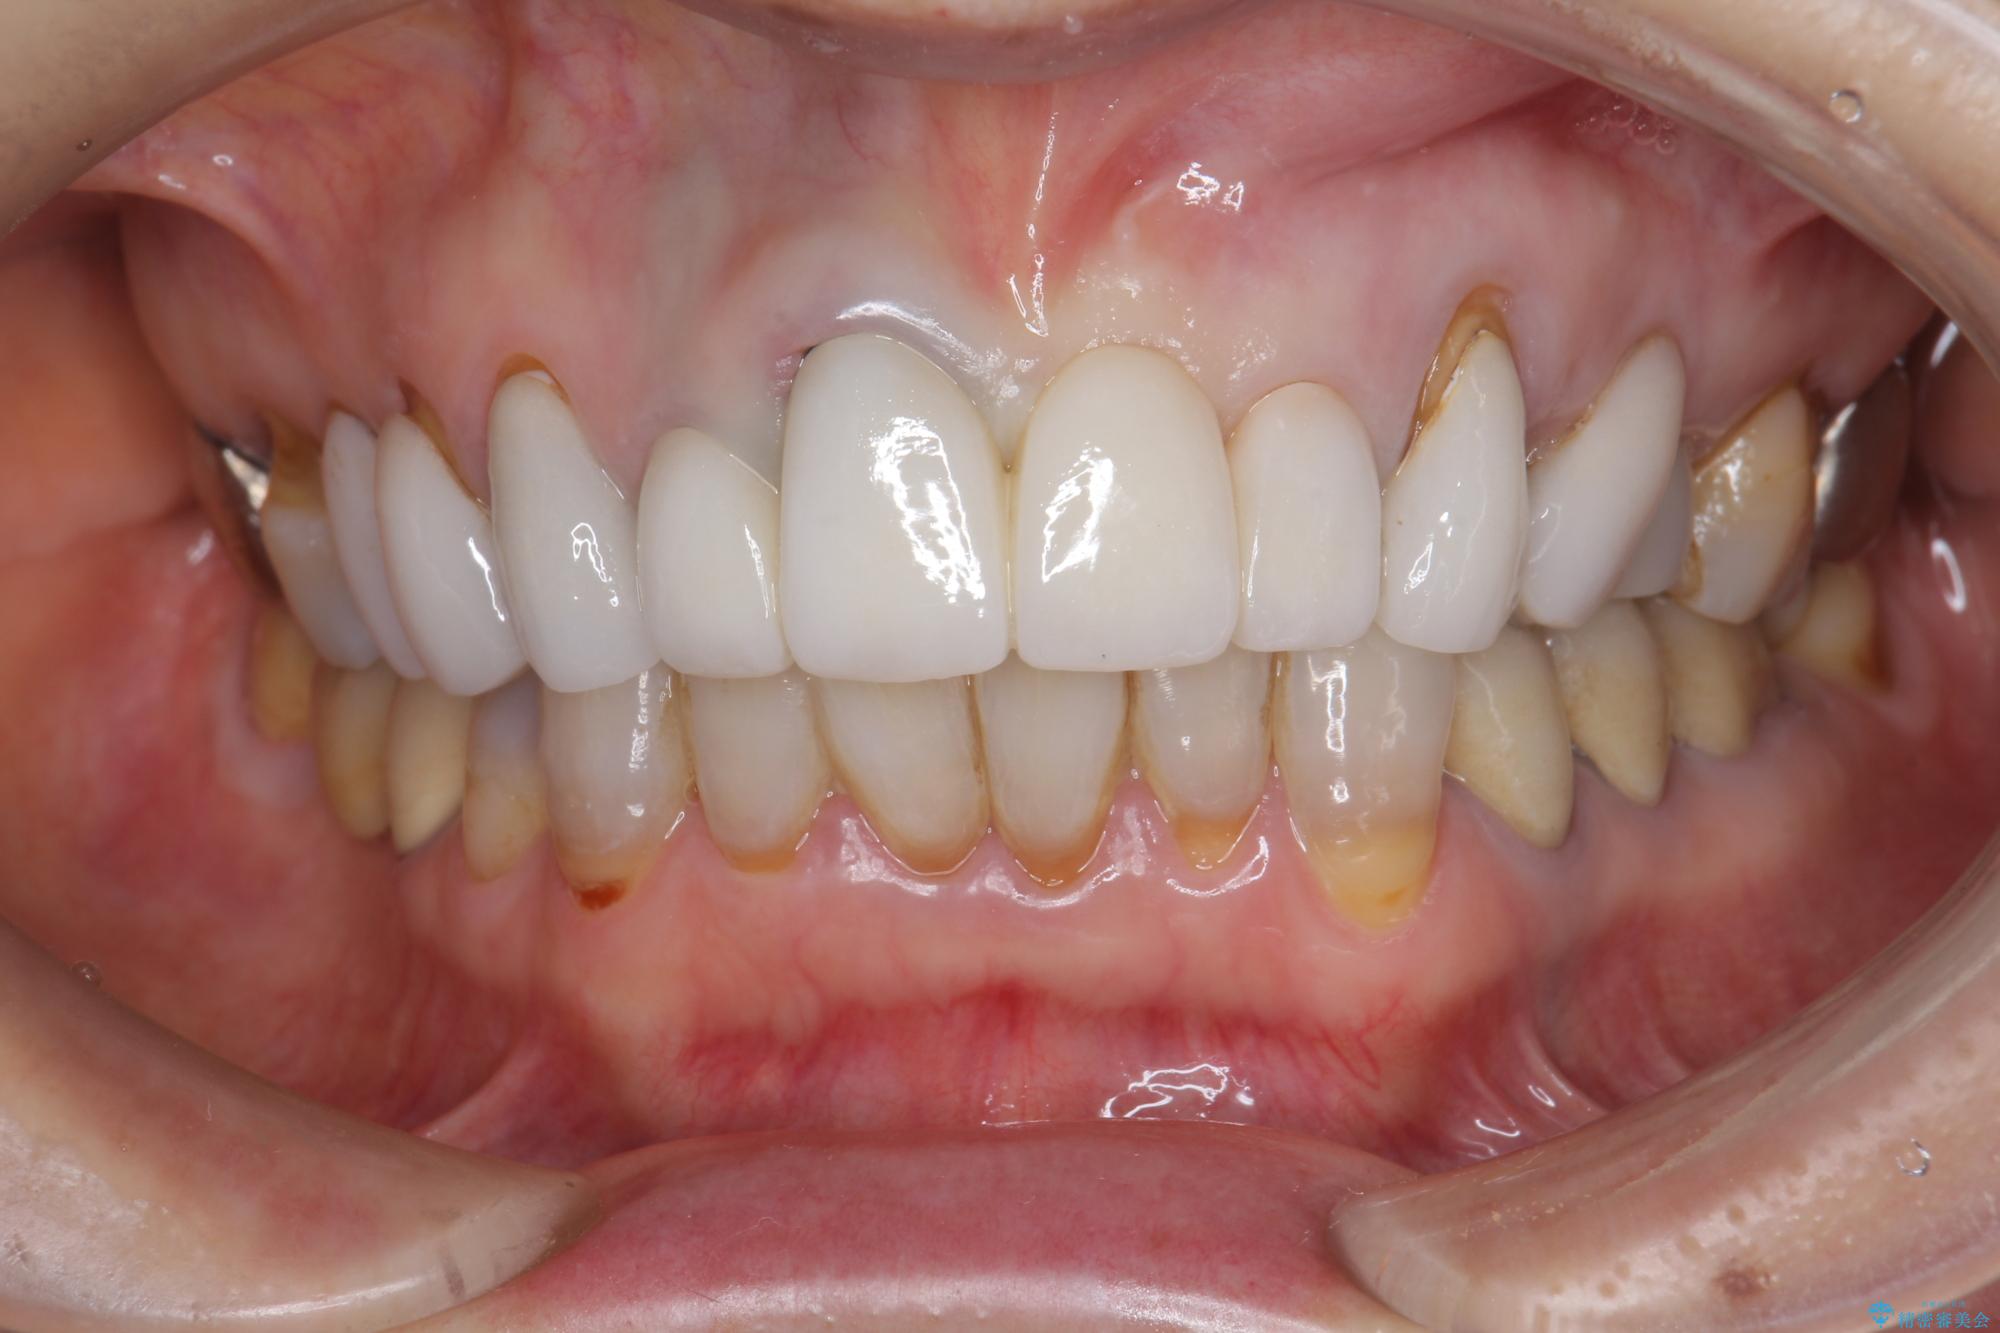

[ セラミック治療 ] 歯ぐきの際の黒ずみを改善したい

- 歯ぐきとセラミックの間の黒ずみが目立つので、きれいに治してほしい。と希望され来院されました。

歯ぐきの位置が変化しクラウン下の歯が見えるようになってしまったことで、審美障害が生じている状態です。

クラウンマージンの再設定を行うことで、黒ずんだ部分を再度覆い、審美障害を改善します。

- 52.8万円(ジルコニアクラウン×4・仮歯×4)費用は治療当時の料金となります